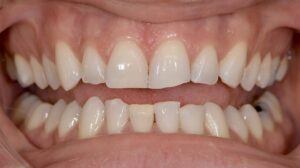

Le congrès de l’EAPD (Académie Européenne d’Odontologie Pédiatrique) a défini des critères de diagnostic en 2003. A savoir des opacités délimités, des fractures post-éruptives, des restaurations atypiques ainsi que que des extractions des molaires. (3) Le diagnostic différentiel doit surtout s’établir entre des amélogénèses imparfaites et des hypominéralisations d’origine traumatique pour les dents antérieures. Cliniquement, les dents vont présenter des colorations blanches ou brunes opaques sur une partie ou sur toute la surface de la dent (Figures 1-2-3-4).

Si en antérieur, le préjudice esthétique n’est pas trop important et qu’il n’y a pas de perte de substance, il est conseillé d’attendre la majorité afin de réaliser un éclaircissement suivi de la technique d’érosion infiltration (ICON), plus ou moins une stratification de composite esthétique (Figures 8-9-10).

Figures 1-2 : Incisives centrales atteintes de MIH

Figures 8-9-10 : Traitement antérieur, éclaicissemet bouche complète, ICON et stratification de

composite sur 11 (l’éclaircissement ayant suffit pour la 41)